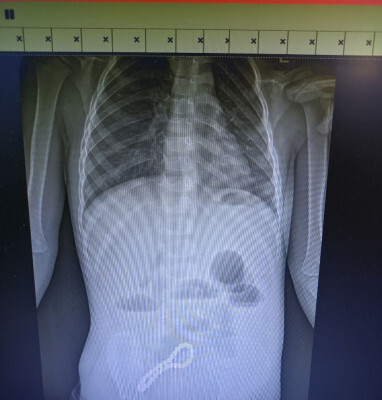

Ребенок попал в больницу с жалобами на проблемы с пищеварением. Медики предположили наличие в ЖКТ инородного тела, что подтвердил рентген.

«Было принято решение об операции. Мы провели минилапаротомию (хирургическое вмешательство, при котором через разрез передней брюшной стенки производится доступ к внутренним органам живота). И увидели, что магнитами, которые притянулись друг к другу, соединены петли кишки; в ее стенке отверстия. В ходе операции удалили все 30 магнитных бусин: 29 маленьких и одну большую», — рассказал хирург больницы Олег Ларькин.